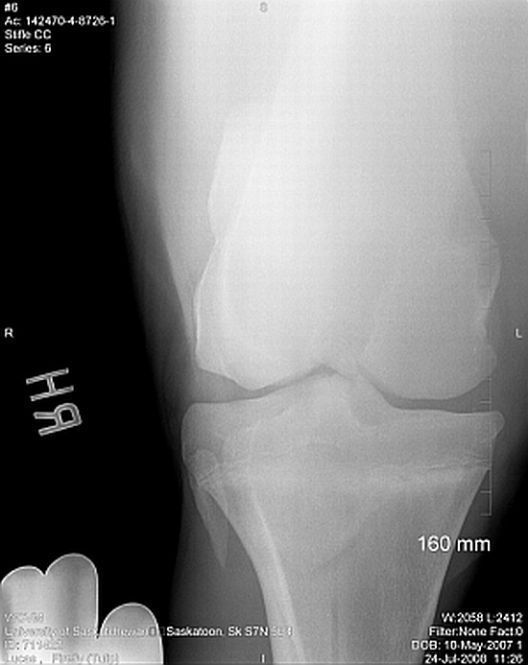

Thank you so much for your assistance, it is really appreciated!! I finally have the cd of the x-rays and will be posting them here. Again, thank you!! The first 2 are stifle pictures, the rest are of the hock.

Right stifle

Thanks Dr. O!! I really appreciate your taking a look at this. I do have Dr. Rantanen's report which is as follows:

Interpretation:

The most proximal portion of the right medial tibial spine was separated by an irregular fracture line. The fragment was still close to its anatomic position.

There was no soft tissue swelling or secondary joint disease present at this time.

Comment:

With the absence of clinical signs of lameness, normal flexion and no soft tissue swelling at this time, this fracture most likely occurred at a young age. It may be an incidental finding in this horse. Success in training would confirm that this fracture most likely occurred at a young age and may be tolerated without surgical intervention.